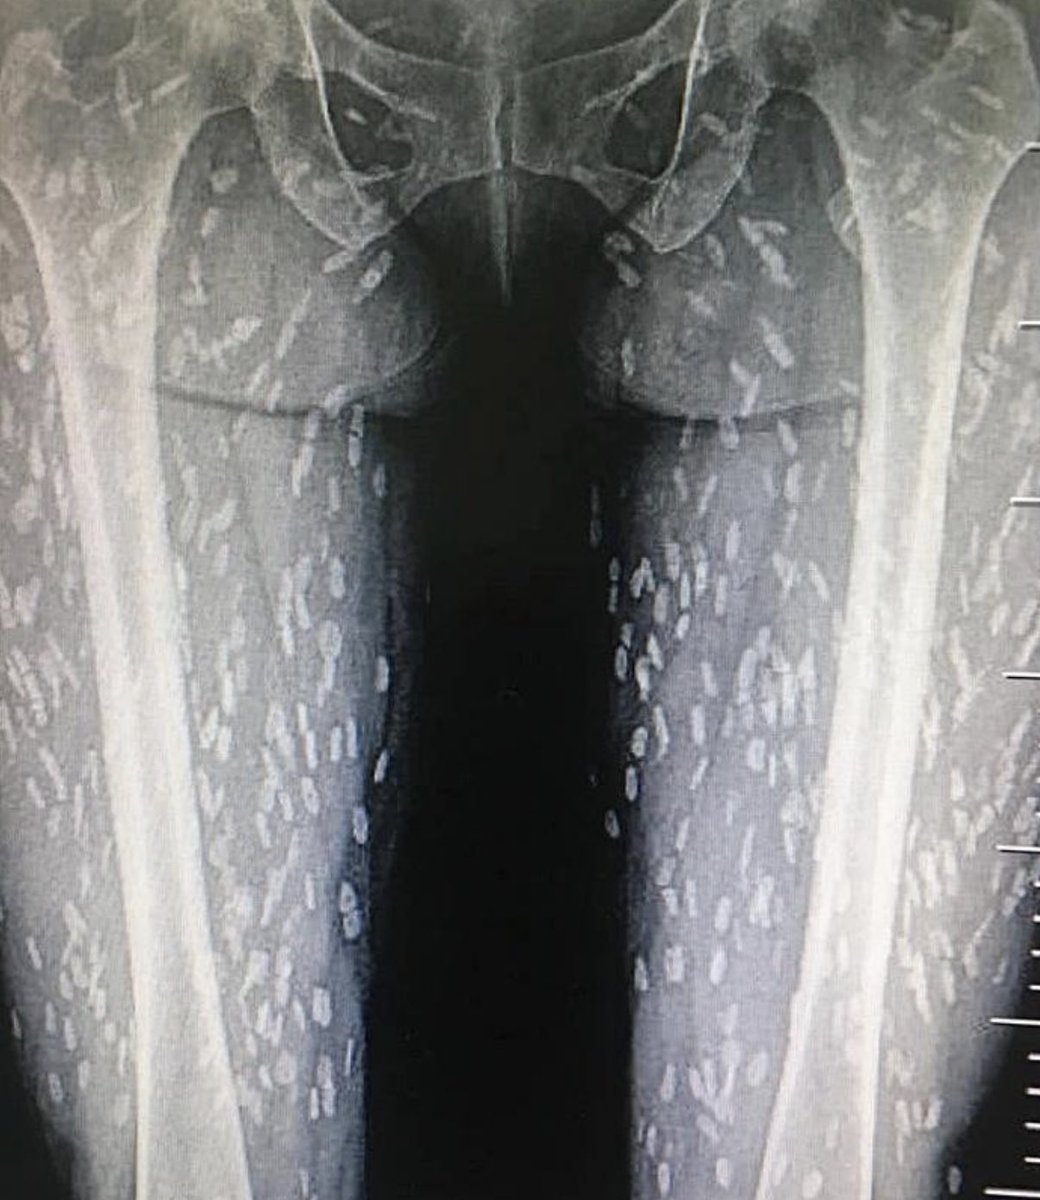

最近、低音処理のレアチャーシューも流行りだけどそのうち有鉤条虫症例も増えてきそうで怖い。 ※写真は豚の生肉を食する文化圏で見つかった重度の有鉤嚢虫(条虫の幼虫)症